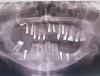

Tatijna Опубликовано 16 октября, 2013 Поделиться Опубликовано 16 октября, 2013 Буду очень благодарна за совет,так я в полном тупике.Мне 59 лет,живу в провинциальном городе.В феврале 2013 мне сделали синус лифтинг вверху справа с одновременной установкой 9 имплантов.Операцию делали под местным наркозом методом напыления туда костного материала,который приобретает клиника(у меня ни каких костных блоков не брали).Врач сказал ждать полгода,пока всё прирастёт.К лету начались выделения из носа,обратилась к лору.Рентген выявил гайморит+один имплант упал в гайморову пазуху.Лор отправил меня к моему стоматологу,который прочистил мне гайморит через пазуху зуба.Причем,одновременно он мне сделал ещё дополнительный синус-лифтинг костной тканью,мотивируя это тем,что надо для надежности ещё подсадить её.Про имплант,упавший в пазуху,сказал,что ничего страшного,он там просто закапсулируется и всё.Отправил меня домой пролечиться и приходить к нему на установку вкладок под постоянные коронки.Месяца три усиленно лечилась медикаментозно.За это время почувствовала,что выкрошилась вся эта костная подсадка(первый раз такого не чувствовала) и чувствовала постоянные выделения из десны над местом,куда вторично подсаживали костную ткань.Там образовался свищ.Прошла томограмму пазух носа:признаки кисты верхнечелюстной пазухи слева и правостороннего гайморита,этмоидита.Теперь уж стоматолог отправил меня в стационар в отделение ЧЛХ на операцию,сказав,что это операция несложная,полежу там денек и всё.В итоге я отбыла там две недели и выписалась почти ни с чем.1.10.13г. сделали операцию"Радикальная гайморотомия по Колдуэллу-Люку.Пластика свища местными тканями.Удаление инородного тела из пазухи".Через несколько дней швы разошлись,образовалась дырка.Полощу рот,а выливается через нос.Через неделю сделали повторную аналогичную операцию.Но вторая была более расширенная,так делали её намного дольше первой,чистили основательно.Обе операции как инквизиция.И вот после второй результат опять тот же:опять дырка в шве и содержимое выливается изо рта в нос.Выписали домой,так как я лежала платно.Дальше предложили 2 недели побыть дома,полоскать рот хлоргексидином и пить ГолдРей,а потом ложиться на третью операцию.И что это результат того,что у меня очень плохая рыхлая слизистая,они считают,что это из-за имплантов.У меня ещё другие импланты торчат в гайморову пазуху,в ЧЛХ мне их порекомендовали лучше убрать совсем,хотя бы из правой проблемной пазухи,так как навряд ли на них долго продержатся коронки.Но сказали,что удалить их возможно опять же через такую операцию.К моему стоматологу идти на консультацию бесполезно,он считает,что как только я вылечу гайморит,можно ставить коронки.Вот теперь на распутье:1.Ложиться на третью операцию,чтобы попытались так зашить шов,чтобы он зажил(что-то в это уже не верю).2.Ложиться на третью операцию и попросить,чтобы убрали 2 импланта сверху справа.В этом случае что предпринять дальше?Реально ли сделать потом на этом месте подсадку кости и поставить импланты?У себя в городе делала в самой дорогой клинике у лучшего врача и вот результат.Я понимаю,что это и проблемы моего организма,но хотелось бы услышать совет,возможно ли исправить всё это.Если это возможно,я могу приехать в любой город(Москву,Питер,Самару и т.д.),возможно там врачи смогут мне помочь.Сейчас у меня сняты все временные коронки,которые мне делали после первой операции.Вот мои снимки.Первый снимок сделан 26.02.13г. сразу после операции синус-лифтинг с установкой всех имплантов.А второй снимок 18.0913г.с упавшим в гайморову пазуху имплантом. Ссылка на комментарий